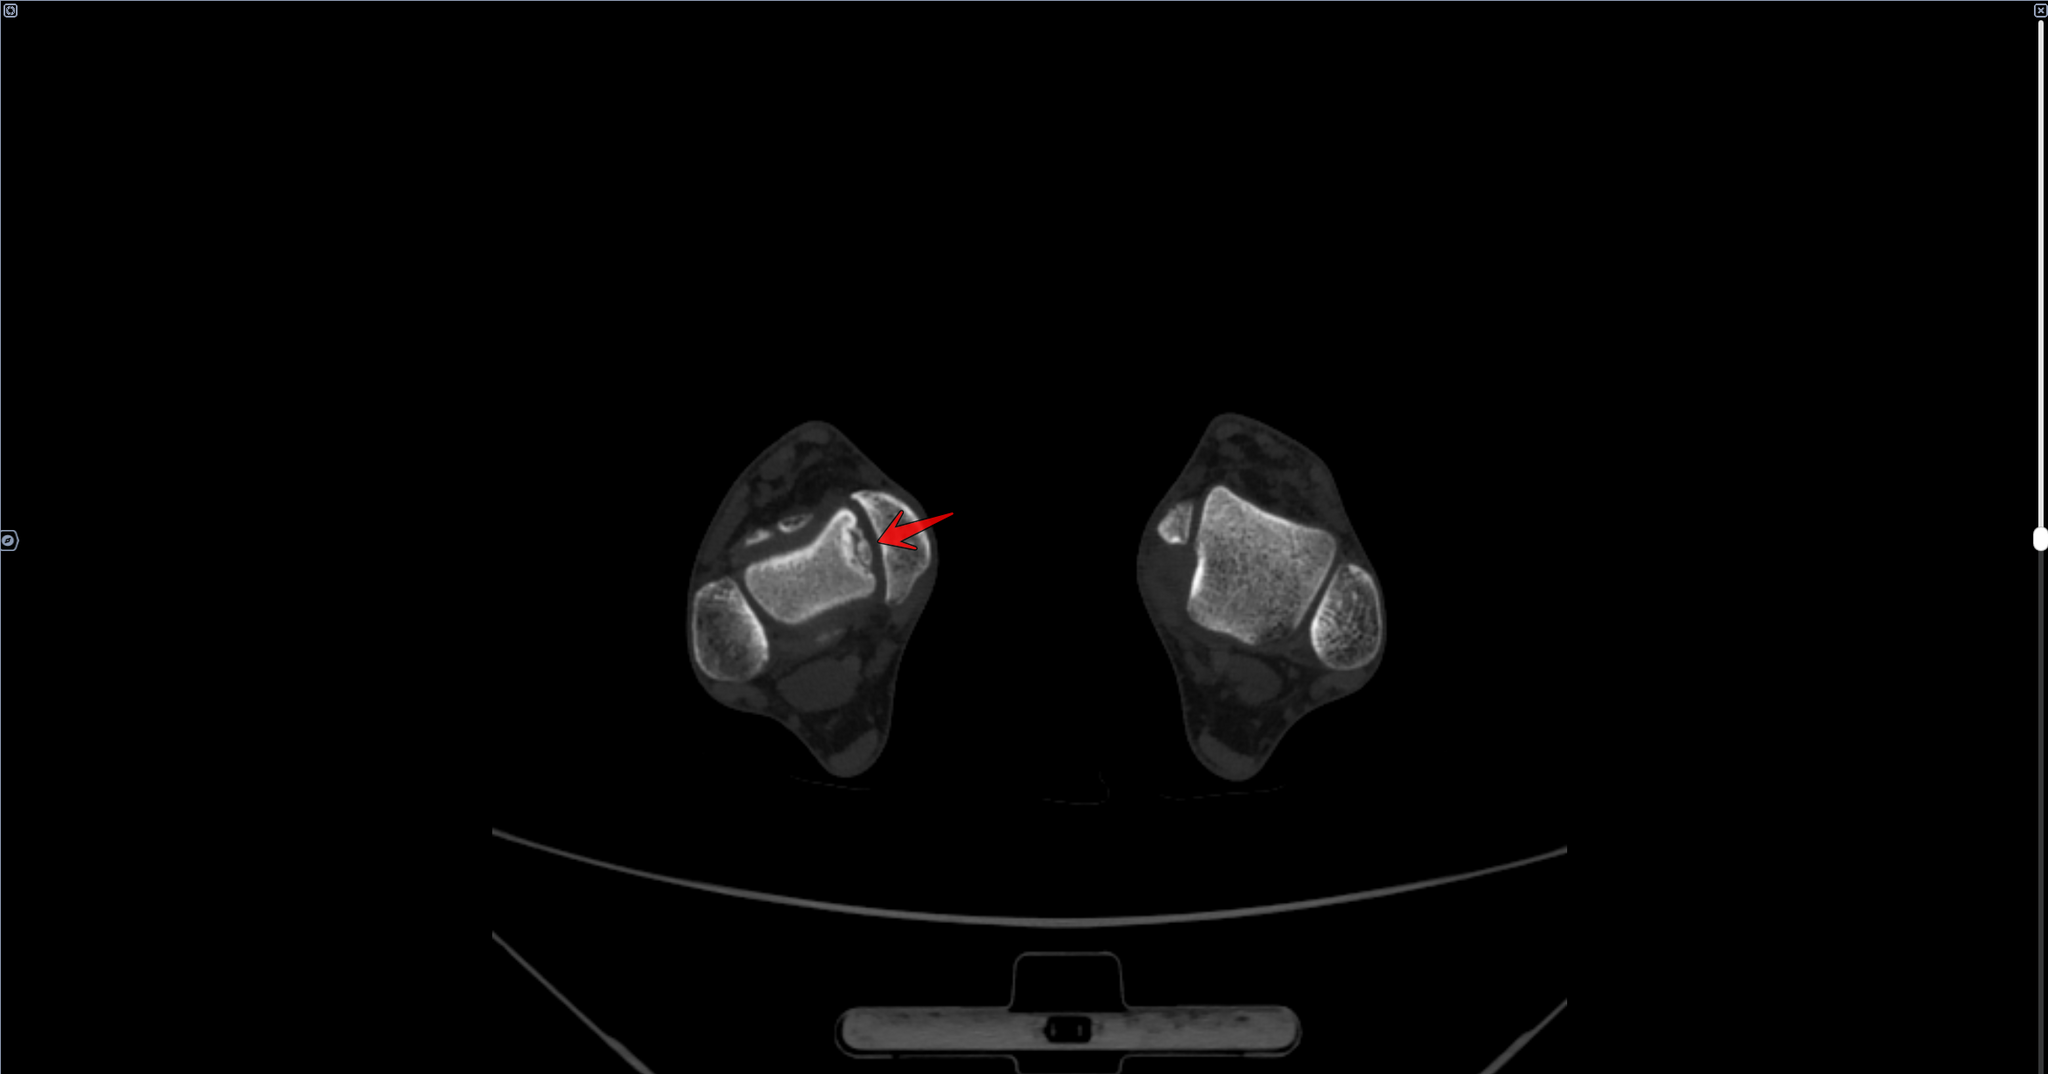

Кейс призывника с рассекающим остеохондритом(б.Кенига) таранной кости(КТ+МРТ)

Призывником были выполнены КТ И МРТ правого голеностопного сустава в частных клиниках.

Описание КТ: по верхне-внутреннему контуру суставной пластинки таранной кости определяется фрагментация кости в виде сгруппированных фрагментов на участке 11х5х6 мм, в ложе кости, отграниченным ободком остеосклероза до 3 мм шириной, перифокально кистовидная перестройка губчатой кости. Заключение: Рассекающий остеохондрит правой таранной кости 3-4 ст.